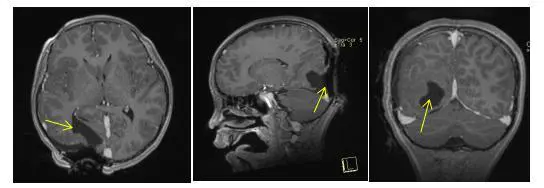

术后影像:术后肿瘤占位被全部切除,无出血迹象,无颅内压增高迹象,术后咬合正常,骨盖位置正常。

术前术后影像对比: